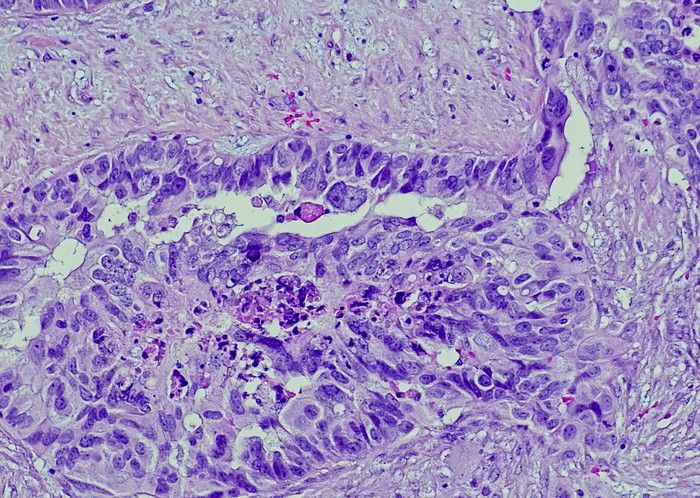

Featured photo at top of ovarian cancer cells. Photo/OGPhoto/iStock.